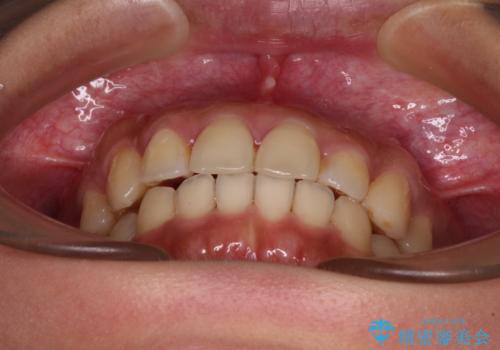

【モニター】歯列が狭くデコボコが気になる 急速拡大装置を用いたインビザライン矯正

- 奥歯の咬み合わせと治療を放置したまま奥歯を気にして来院された患者様です。

上顎骨の幅が下顎骨よりも小さいので、拡大装置により骨幅を広げて上下関係を改善し、その後インビザラインにて歯並びを整えることとしました。

上下の骨幅を改善したことで、スムーズに歯列矯正を行うことができました。

土台のまま放置されていた歯は土台の状態で咬み合っていましたが、急速拡大を行った際に咬み合わせが著しく挙上されたため、その際に土台を大きくすることで咬み合う歯との距離を確保しました。